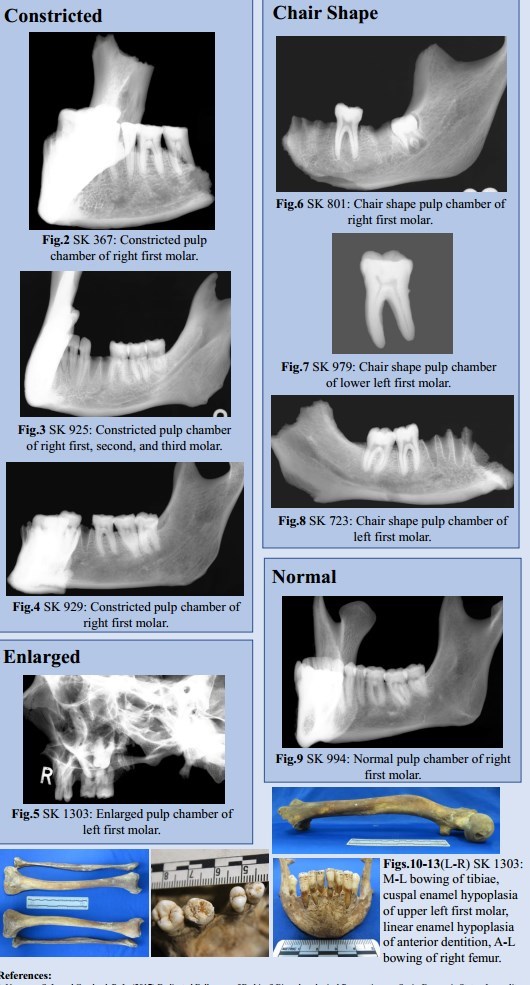

However, 28 individuals exhibited evidence for constricted (N=16) or chair-shaped (N=12) pulp chambers associated with vitamin D deficiency during pulp chamber formation.

One adult male aged 18-25 years exhibited a normal pulp chamber.

One further adult male aged 26-35 years exhibited an enlarged pulp chamber. This molar has an abnormal, poorly mineralised occlusal surface consistent with cuspal enamel hypoplasia (CEH) (Fig. 11).

Of the 30 individuals analysed, 28 exhibit morphological changes to the pulp chamber consistent with vitamin D deficiency. Deficiency must occur during pulp chamber formation for morphological changes to arise (1.5-2 years in males, and 1.4-2 years in females), therefore these results suggest that the vast majority of adults in this sample group experienced prolonged vitamin D deficiency ~1.5 years of age.

Two individuals exhibit change in the first, second, and third molars, indicating chronic or recurring deficiency throughout childhood. Neither exhibited skeletal evidence for vitamin D deficiency.

SK1303 exhibited an enlarged pulp chamber. Clinically, this has been linked to both vitamin D- resistant hypophosphatemic rickets and odontogenesis imperfecta.6 This individual is currently the subject of further research, as they also exhibit skeletal change consistent with residual rickets (See Figs.10-13).